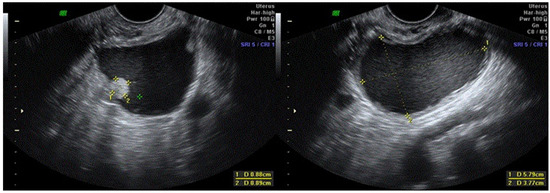

| 4 | 28 | 0 | Right | 40 | Unilocular cystic low-level echogenicity | Yes | None | Borderline serous tumor | 54 | Normal follow-up, no recurrence. Spontaneous pregnancy. |